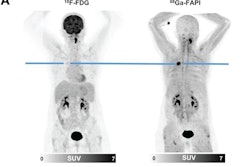

- Enhanced therapeutic opportunities. Theranostics has opened new horizons for nuclear medicine, such as targeted radionuclide therapy, which can be used to treat e.g., prostate cancer and thyroid disorders. Close cooperation allows for seamless integration of high-resolution diagnostic imaging data (anatomical targets) with functional data (treatment response assessment and optimized therapy delivery).

- Improved patient management. Collaboration will streamline patient management workflows, e.g., optimized scheduling, reduced wait times, and enhanced overall efficiency. It will allow for integrated diagnostic reports with findings from both disciplines and facilitate informed decision-making and personalized treatment strategies. Also, it will ensure new and exciting developments such as theranostics aren't hijacked by clinicians and organ specialists, who may lack the profound understanding of anatomy and pathophysiology needed to treat patients adequately.

The bone of contention has everything to do with the growing role of theranostics, i.e., radioligand therapy which uses the same target for both imaging and treatment. Theranostics has the potential to become a game changer in cancer care. However, there is a very real concern that theranostics may be taken over by specialists in radiation oncology, urology, oncology, neurology, and endocrinology. Close collaboration between diagnostic imaging and nuclear medicine specialists provides the best opportunities for patient-centered workflows and integrated care. This view is often not shared by medicine physicians, most of whom would prefer to collaborate with clinicians and ‘embed’ theranostics within an oncologic practice.

When two dogs fight for a bone, a third may run away with it, and I am very much afraid this could happen with theranostics. While radioligand therapy offers great opportunities for patients, setting up the infrastructure does pose a challenge to healthcare authorities and payers. A strong alliance between diagnostic imaging and nuclear medicine can assist in careful patient selection, streamlined workflows and optimized patient care, with the ability to assess treatment results through quantifiable imaging biomarkers. These opportunities could be lost in a ‘vertically integrated’ model, with oncologists or organ specialists controlling and managing the treatment.